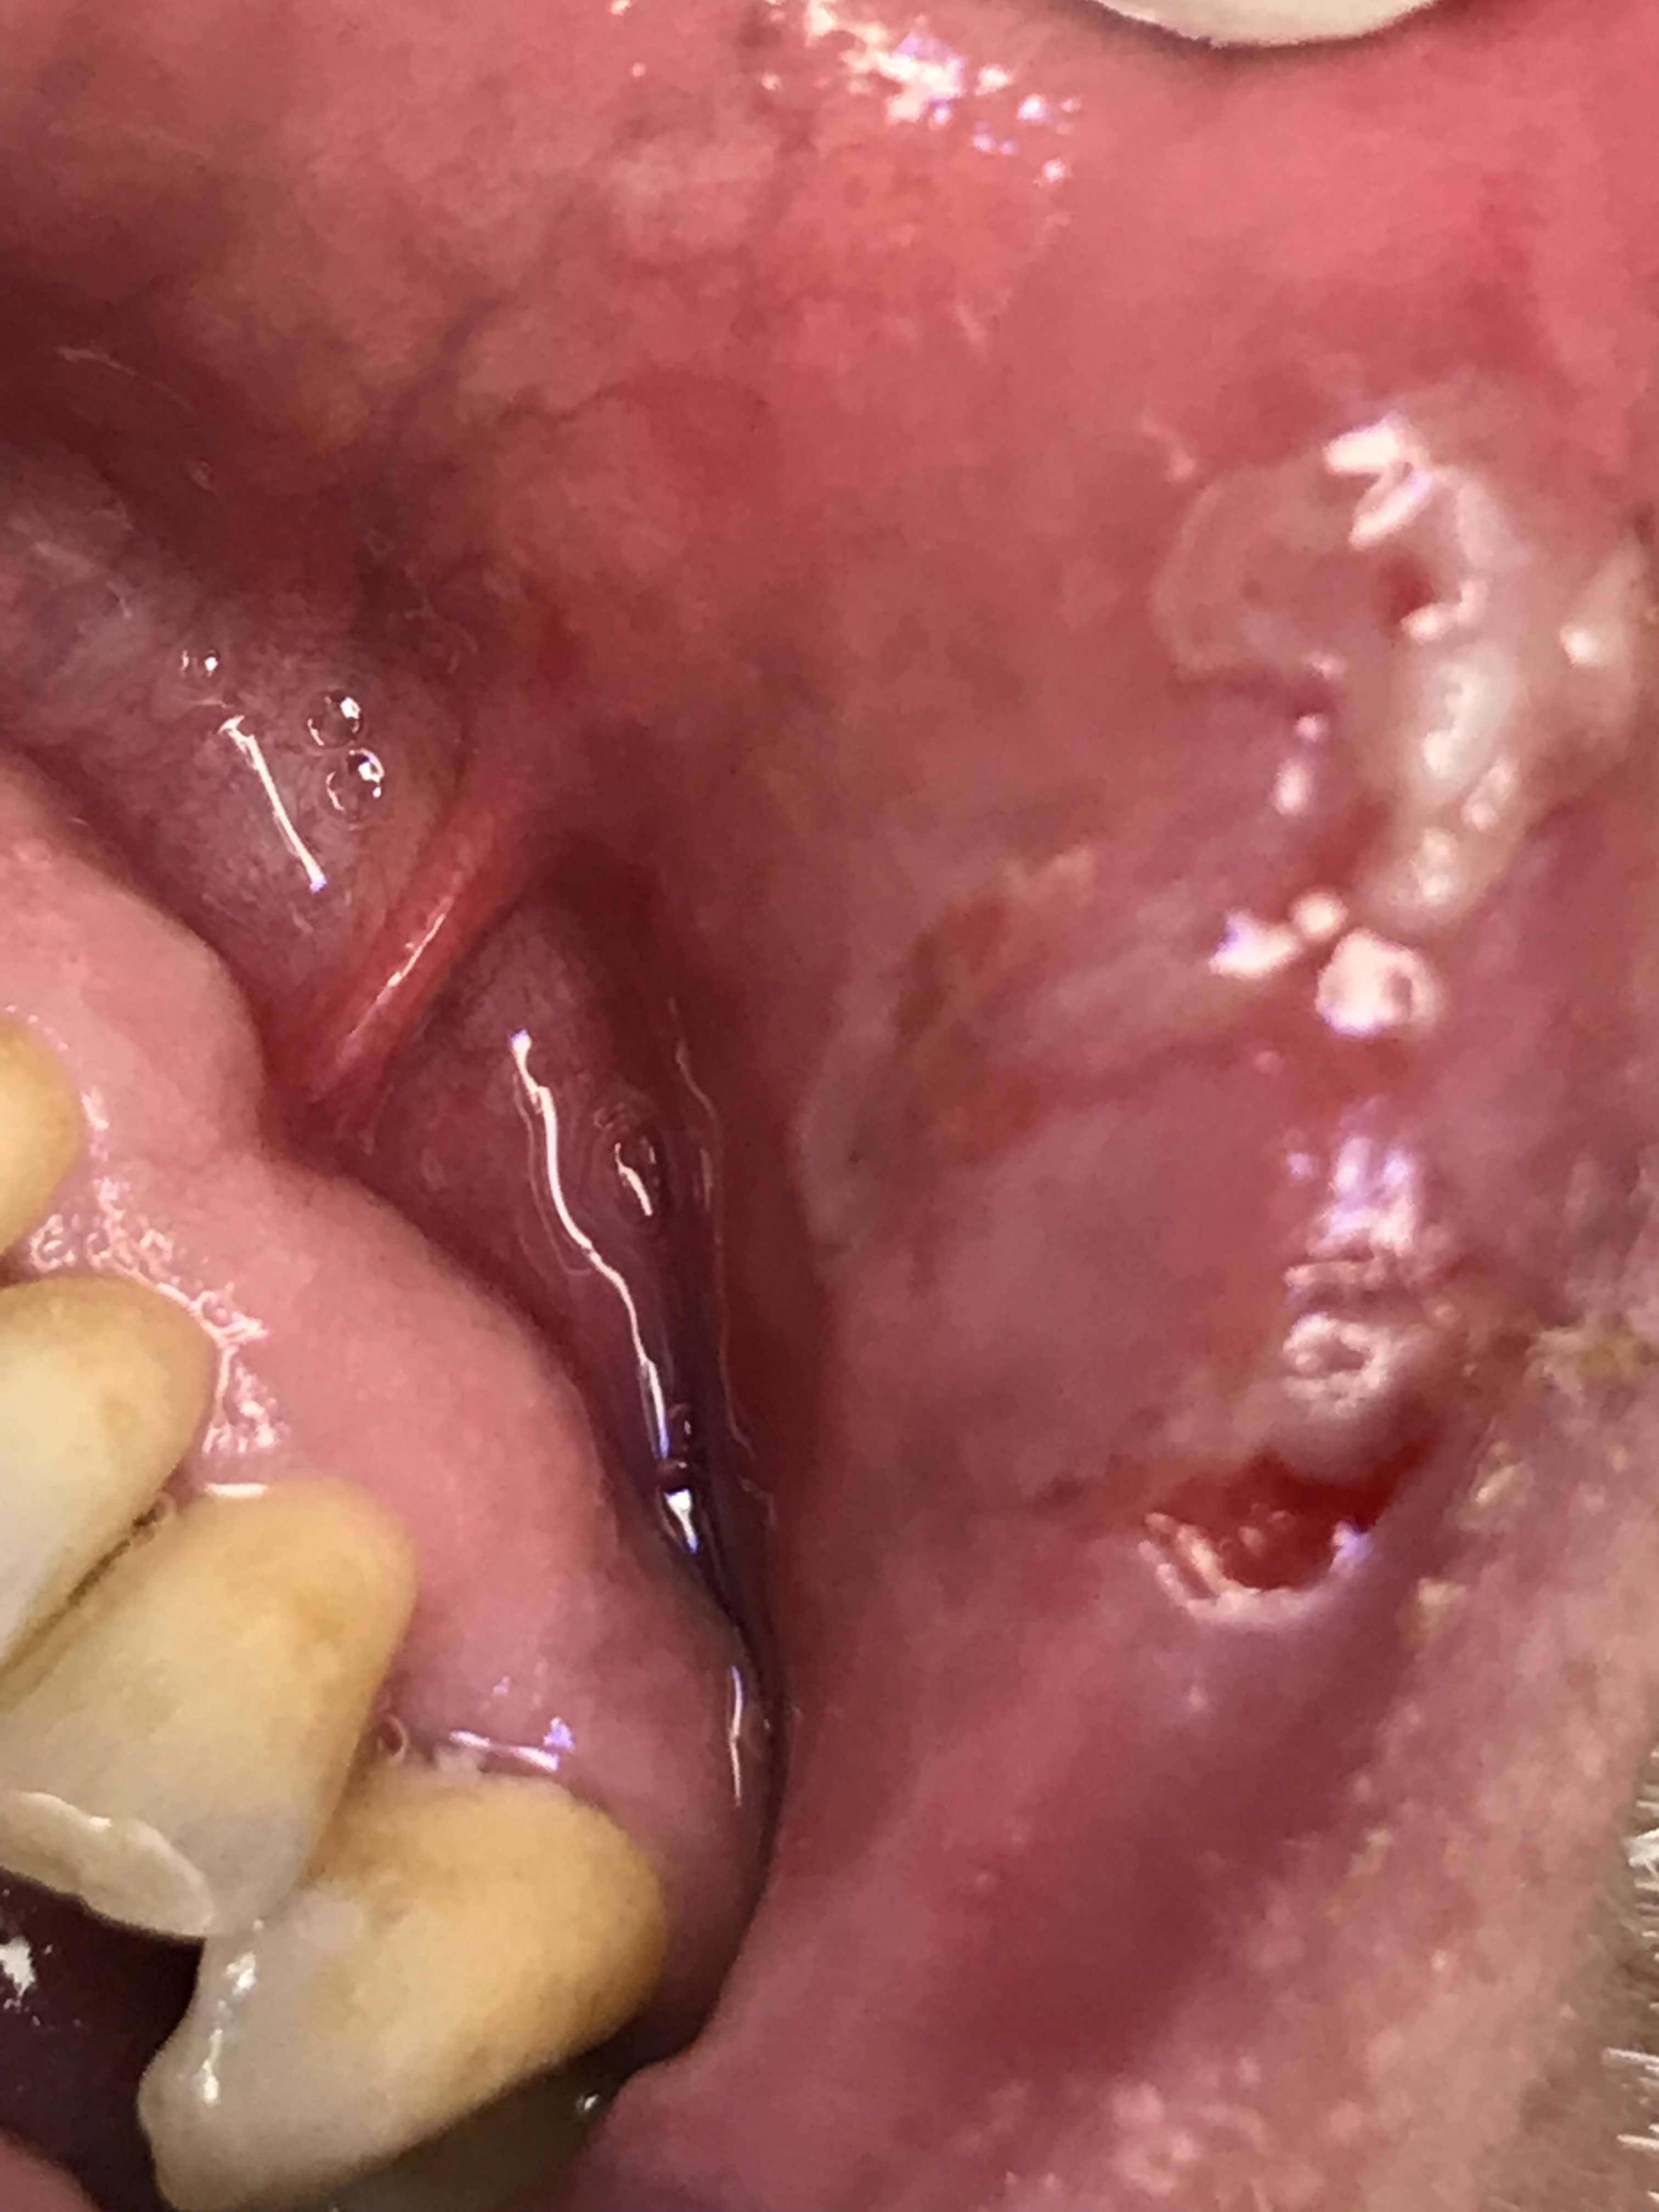

Hokusai tiens ça va te plaire ça : gros aphte à faire partir au laser . Il en a plusieurs. Un par séance car le deuxième dans la séance est à moitié prix sinon